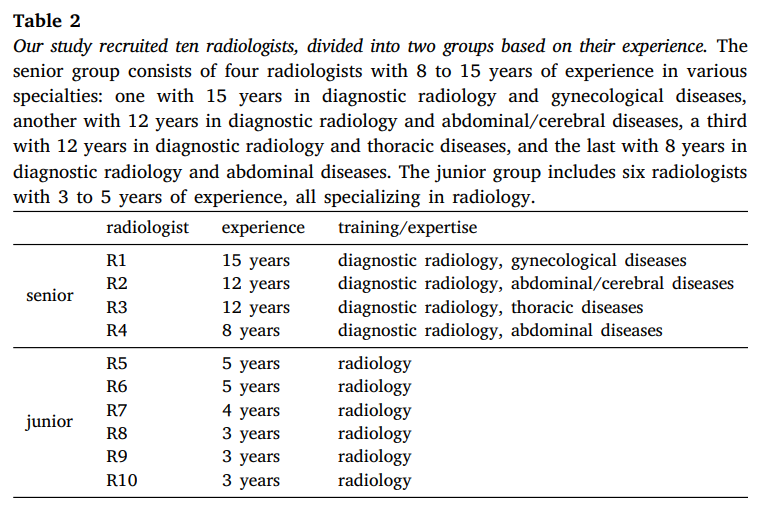

我们的研究招募了十名放射科医生,包括四名具有8至15年经验的资深放射科医生和六名具有3至5年经验的初级放射科医生。详细信息如表2所示。为了确保注释的准确性和一致性,所有放射科医生都熟悉了以下描述的注释标准。我们使用的工具包括Pair的许可版本和开源的3DSlicer进行注释和修订。我们为AbdomenAtlas中的25个结构提供了注释标准,包括16个腹部器官(食管、胃、十二指肠、肠道、结肠、直肠、肝脏、胆囊、脾脏、胰腺、左肾、右肾、左肾上腺、右肾上腺、膀胱、前列腺)、2个胸部器官(左肺、右肺)、5个血管结构(主动脉、腹腔干、下腔静脉、门静脉和脾静脉、肝血管)以及2个骨骼结构(左股骨和右股骨)。图2展示了一个详细注释的CT体积示例。